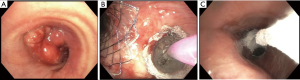

Tumors causing CAO are primarily described by their location in relation to the lumen of the airway: endoluminal, extrinsic, or mixed (Figure 1). Other key factors to consider when classifying CAO are location and degree of stenosis. Together, these three characteristics contribute to symptomatology, define treatment options, and predict treatment outcomes. While endoluminal tumors typically require debulking, extrinsic compression of the airway can be treated with dilation and potentially stenting. Treatment of obstructions with both endo- and extraluminal components utilizes a multi-modality approach (Figure 2).

Figure 1 Types of malignant central airway obstruction: (A) endoluminal obstruction secondary to carcinoid tumor originating from the right upper lobe; (B) primarily extraluminal obstruction from left lower lobe subsegmental compression; (C) mixed obstruction from right paratracheal mass with endotracheal extension.